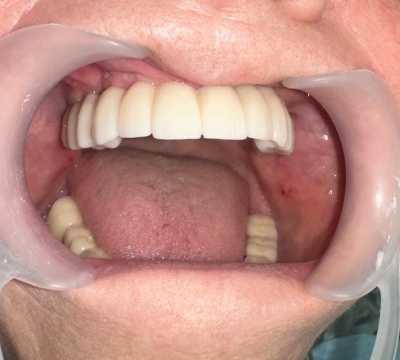

Lucrări fixe cimentate la nivelul maxilarului din ceramica pe zirconiu

Reabilitarea orala funcțională și estetică, s-a realizat cu ajutorul unei lucrări fixe cimentate la nivelul maxilarului din ceramica pe zirconiu și a 3 lucrări din ceramica pe zirconiu fixe cimentate la nivelul mandibulei.